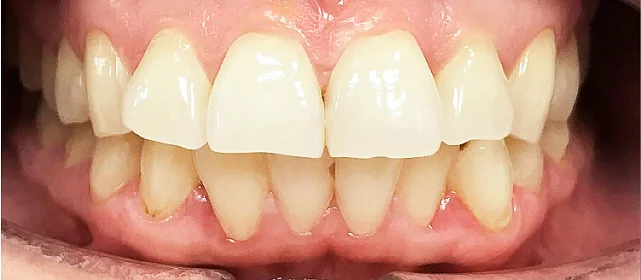

Неровные зубы, неправильное смыкание.

Нарушение соотношения челюстей и неправильное положение зубов — зубные ряды смыкались некорректно, зубы стояли со смещением.

Проблема: В клинику обратилась пациентка — беспокоили неровные зубы и неправильное смыкание. Зубные ряды сходились некорректно, зубы стояли со смещением, что влияло и на внешний вид, и на распределение нагрузки при жевании.